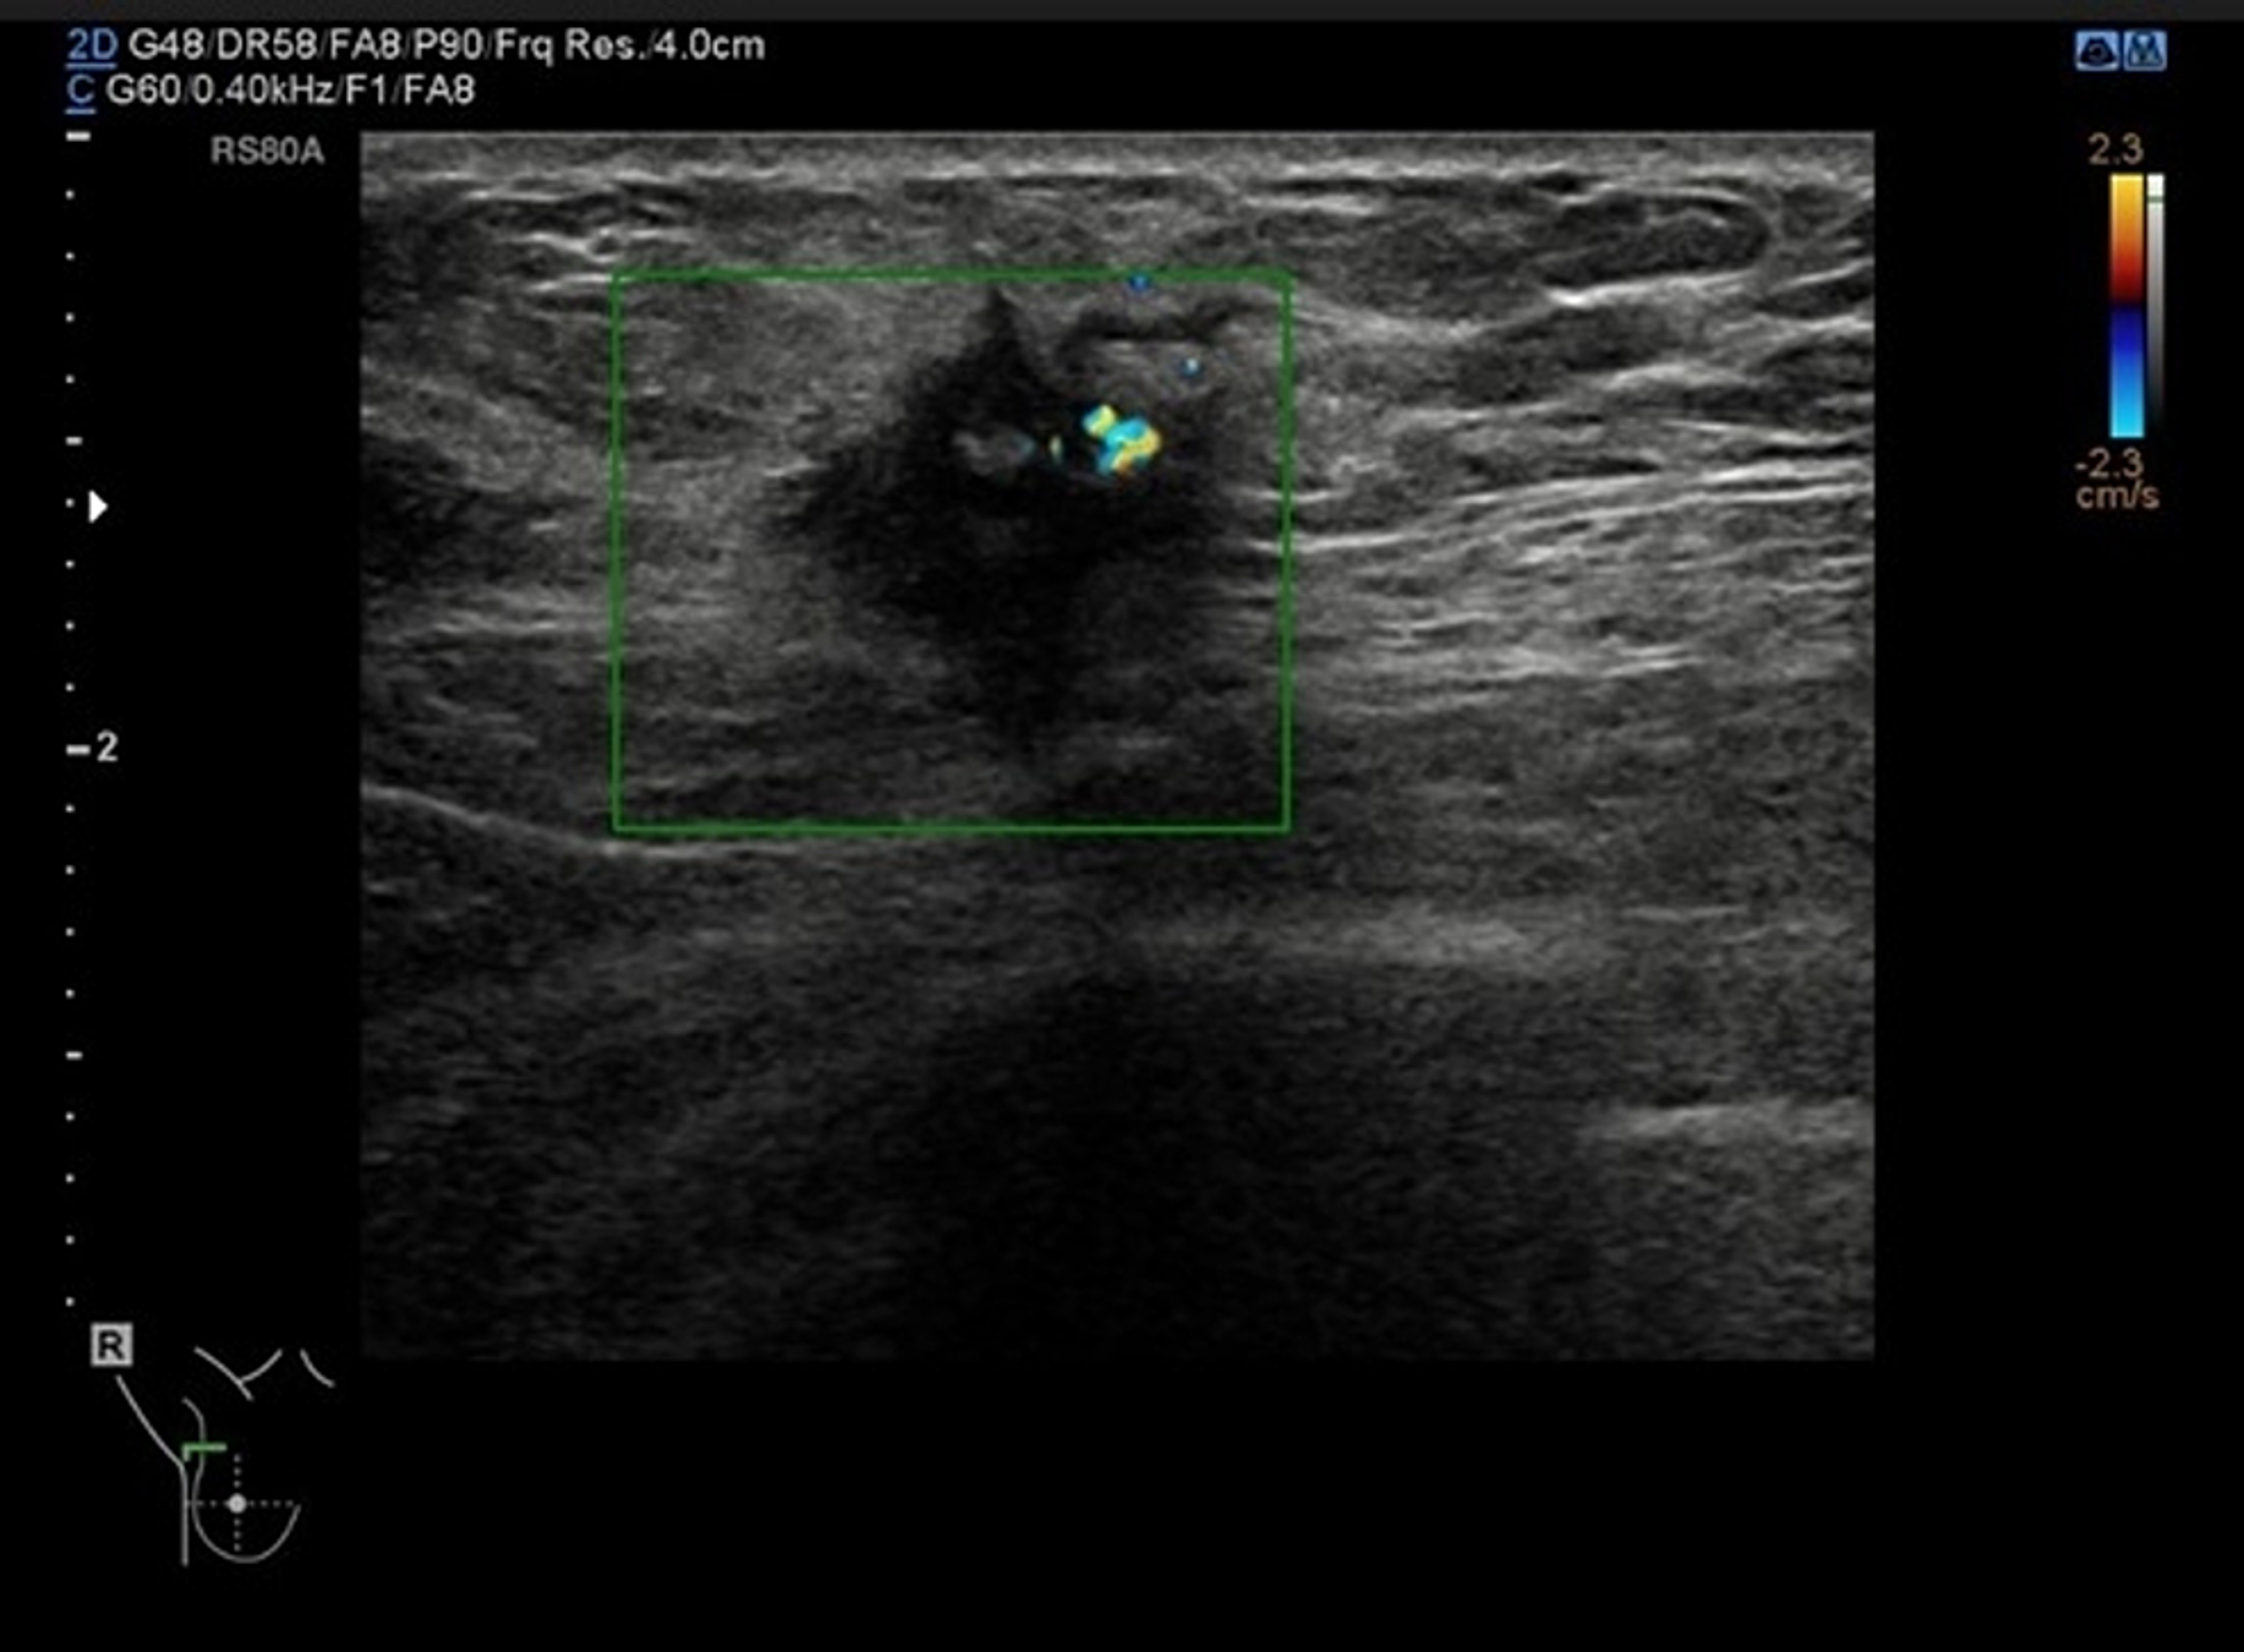

Mammogram (Figure 1) showed a 25-mm suspicious lesion in the right axillary tail, which was also visualized on ultrasound (Figure 2), along with a suspicious lymph node in the right axilla. Imaging-guided core biopsies were taken from both; the histopathology was consistent with grade 1 invasive ductal carcinoma, and ER 0, PR 0, and HER 2 negative as well. Mastectomy with axillary clearance was performed after consultation with breast MDT (multidisciplinary team). The post-operative histopathology revealed 23-mm, grade I, triple-negative invasive ductal carcinoma (Figure 3) with lymphovascular invasion, Ki67 10%, one out of nine lymph nodes showing metastatic disease, and the final staging as T2N1M0. The MDT advised for annual surveillance for five years.